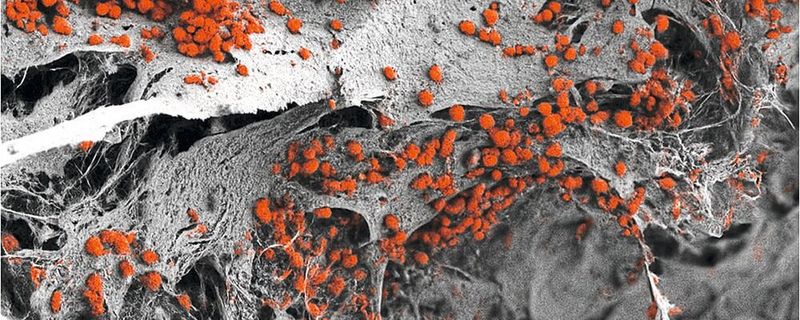

Rasterelektronenmikroskopische Aufnahme des künstlich hergestellten 3D-Knochenmarkgewebes, das mit menschlichen Blutzellen (rot) besiedelt ist. (Bild:  Andrés García García, Universität Basel, Departement Biomedizin)

Rasterelektronenmikroskopische Aufnahme des künstlich hergestellten 3D-Knochenmarkgewebes, das mit menschlichen Blutzellen (rot) besiedelt ist.

Die Forschenden integrierten diese Zellen in das künstliche Knochengerüst, stimulierten spezifische Differenzierungsprozesse und ließen auf diese Weise reproduzierbar eine Vielzahl verschiedener Zellarten des Knochenmarks heranwachsen. Ihre anschließende Analyse bestätigte, dass dieses dreidimensionale Konstrukt der Zusammensetzungder endostealen Nische des Knochenmarks deutlich näherkommt als bisherige Modellsysteme. Es ist mit acht Millimetern Durchmesser und einer Dicke von vier Millimetern auch größer. Das Konstrukt erlaubte den Forschenden, die menschliche Blutbildung im Labor nachzuahmen.